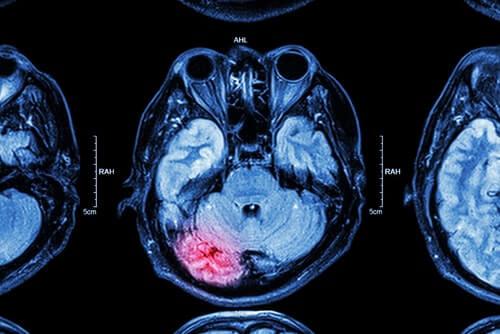

Traumatic brain injuries are a leading cause of disability and death in the United States. Traumatic brain injuries, or TBIs, are caused by a force being exerted on the brain, which can cause severe damage.

A TBI is any bump or blow to the head that affects the brain’s function. A traumatic brain injury can be caused by a penetrating injury or a non-penetrating injury.

A penetrating or open head injury happens when an object pierces the skull. Conversely, non-penetrating injuries, or closed head injuries, occur when an object causes the brain to shake inside the skull but does not break through the skull.

Long-Term Impairments from a Severe TBI

A traumatic brain injury can disrupt brain function, leading to permanent disability and death. Each year, over 282,000 hospitalizations are related to traumatic brain injuries, or TBIs, with 153 people dying from a TBI daily.

A traumatic brain injury is usually the result of a forceful blow or strike to the head. It may occur if your head comes into contact with an object, like if your head hits the dashboard during a car accident. A TBI can also occur if a falling object hits your head, like a piece of scaffolding that falls from a construction site.

If the head trauma does not involve penetration of the skull, it is known as a closed head injury. In contrast, an open head injury, or penetrating trauma, is more likely to cause brain damage since it pierces through the skull and directly into brain tissue.